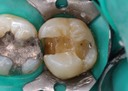

Joe Cha #19 pre-op